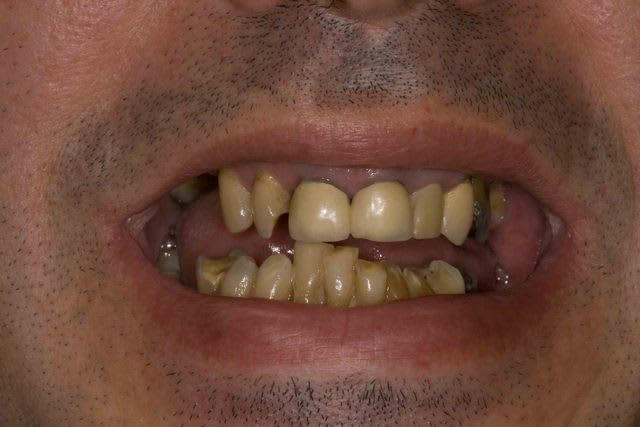

Mais la, apres 1 an de traitements reguliers, entre les lambeaux d'assainissements, les élongations coronaires et les reprises de traitements pourrave j'ai enfin BOUCLE CE CAS !

A l'origine le patient ne voulait surtout pas touché aux dents encore " saine" car il les trouvait bien.

Maintenant il les trouve jaunes et veux les blanchir. Comme quoi un nouveau sourire amene souvent un nouveau regard.

Pour l'egression des dents mandibulaire le patient ne voulait SURTOUT pas toucher au dents encore "saines" .

"Chaques fois qu'on ma touché une dent j'ai eu un probleme donc si elles n'ont rien touchez les pas svp "dixit le patient. En augmentant la DV de 4 mm j'ai pu eviter les meulages.

Le probleme c'est que maintenant il ne les trouvent pas belles et veut les blanchir/meuler... Sont jamais content les patients.

Pourquoi blanche : toujours selon le patient . "Dr j'ai eu les dents pourris toutes ma vie, aucun dentiste n'a voulu me soigner . Si vous me faites quelque chose je veux que se soit blanc" Amen